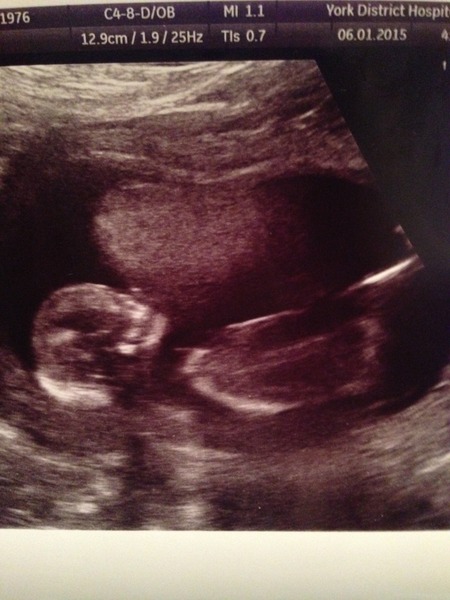

luckythirteen · 06/01/2015 15:17

Lovely clear scan Stone!

Overtiredbackagain · 06/01/2015 15:20

Lovely pic Stone, congratulations!

Number3cometome · 06/01/2015 15:23

StoneBaby woohoo!! lovely pic!!

Congrats stone

Fab pic Stone